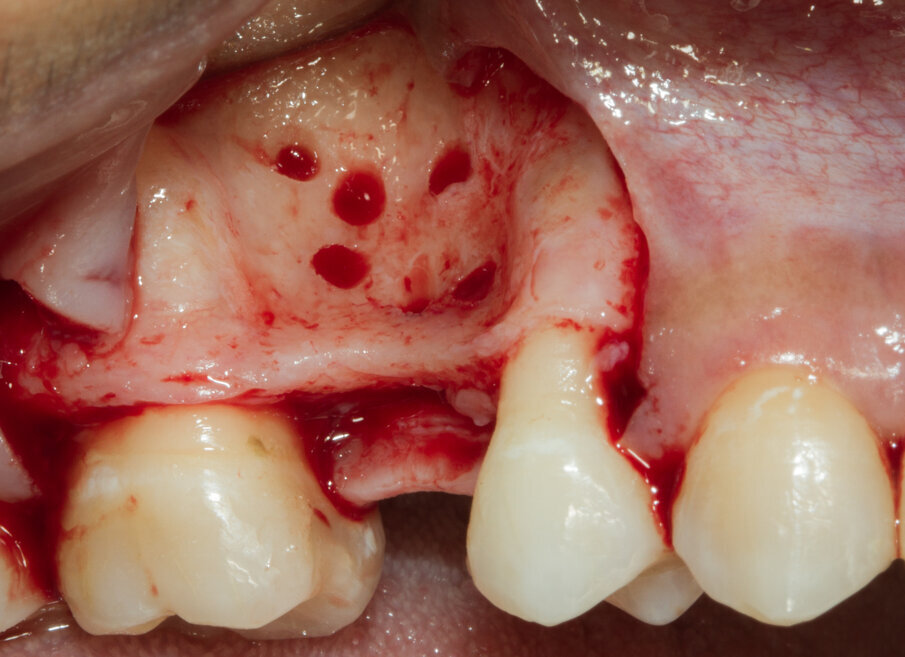

Si programma un intervento di GBR con rigenerazione ossea orizzontale mediante utilizzo di granuli di sostituto osseo eterologo (OsteoBiol Gen-Os) e un device riassorbibile costituito da osso corticale eterologo (OsteoBiol Lamina Soft). A 10 mesi verrà inserito un impianto differito. Dopo aver inciso un lembo mucoperiosteo con incisioni di scarico verticali e scollato sino alla parte più apicale del vestibolo si apprezza l’estrema sottigliezza della cresta residua e la sua corticalizzazione (Figg. 5, 6). Vengono praticati dei fori di 1,4 mm di diametro nella corticale vestibolare per esporre la midollare interna e aumentare la vascolarizzazione del particolato osseo che verrà innestato nel difetto osseo (Fig. 7).

Fig. 7 - Visione vestibolare del difetto osseo.